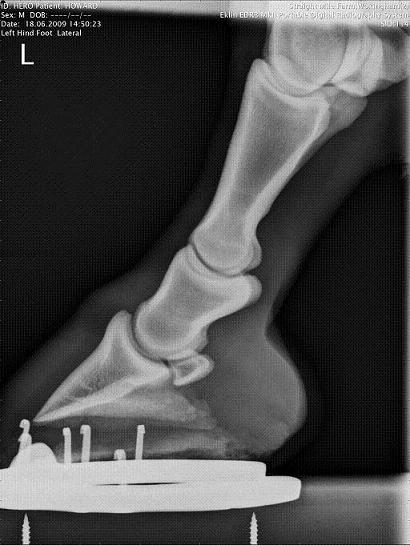

LF Lateral

Left hind Lateral ( only xray i have and only done for comparison to febs xrays - which i do not have )

LH Lateral

3) I cannot count how many horses with both diagnosed and undiagnosed lameness of the foot that were remarkably more sound with proper balancing, squaring off of the toe, and rockering the bottom of the foot or shoe. The LF lateral above suggests to me there is a fair about of horn out in front of the coffin bone to deal with. Maybe instead of you talking to the vet you need to put the vet in touch with the farrier.